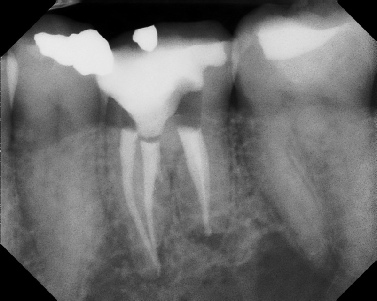

Pre-op Post-op 1 Post-op 2